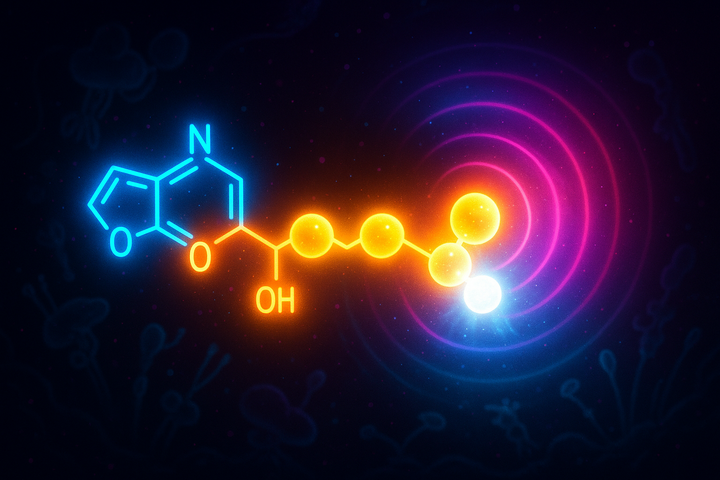

We've traveled through Gibbs free energy from formula to function—from ΔG = ΔH - TΔS to protein folding, membrane potentials, and the persistence of diamonds.